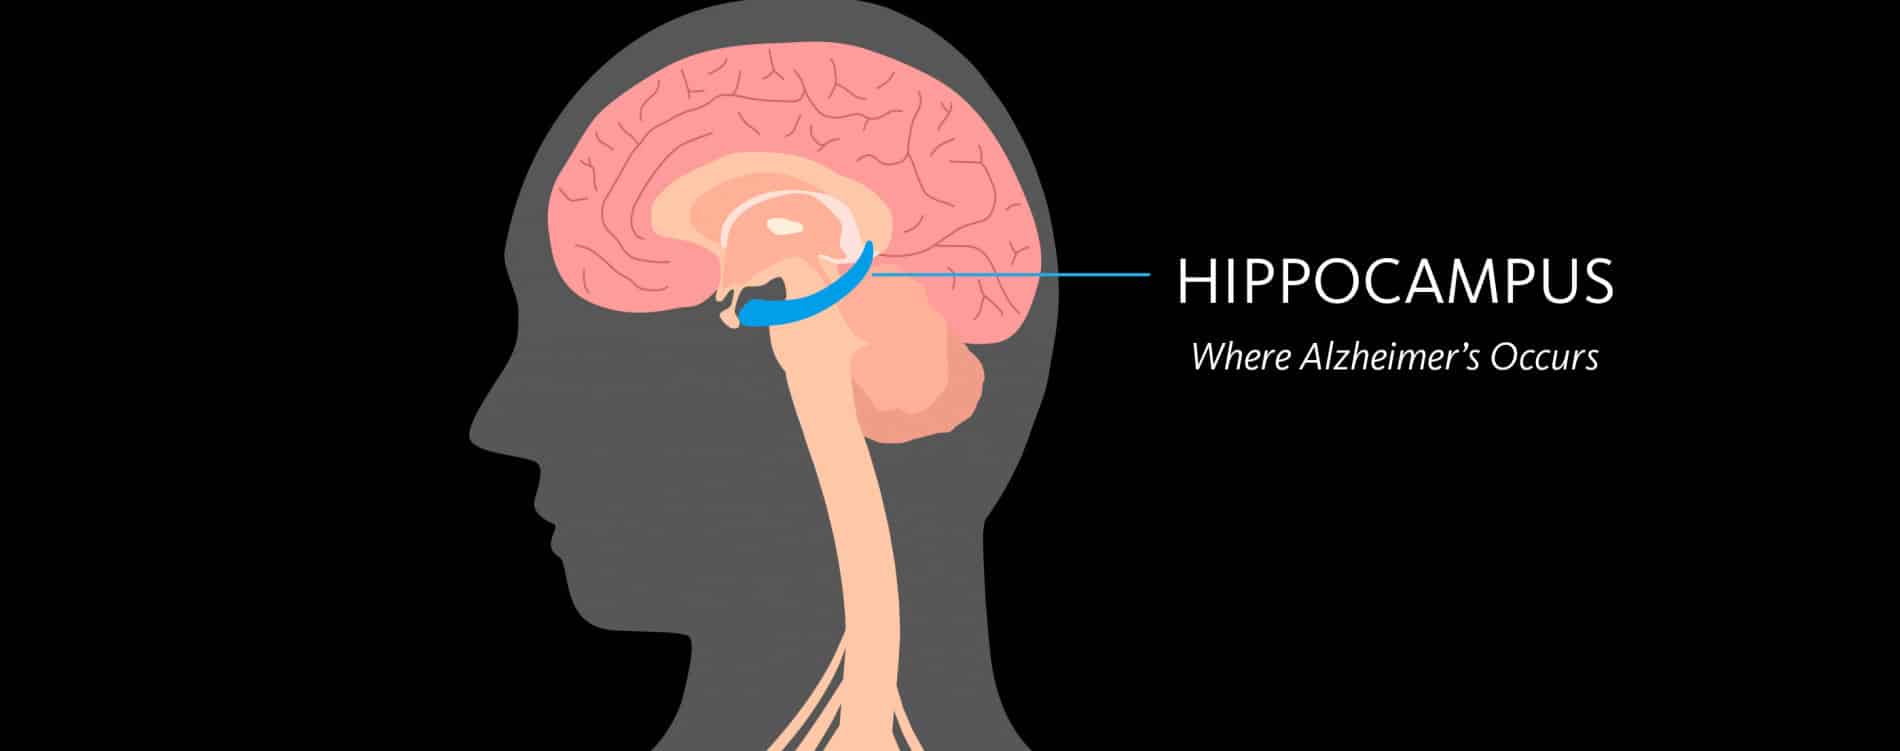

Αλτσχάιμερ γονίδια: Η νόσος του Αλτσχάιμερ (LOAD) είναι η πιο κοινή μορφή άνοιας στους ηλικιωμένους, που πλήττει σχεδόν 44 εκατομμύρια άτομα παγκοσμίως. Παρά τις δεκαετίες έρευνας, οι γενετικοί παράγοντες που προδιαθέτουν τα άτομα στο LOAD δεν είναι κατανοητοί. Με έναν αυξανόμενο ηλικιωμένο πληθυσμό στις ΗΠΑ και σε πολλές άλλες ανεπτυγμένες χώρες, υπάρχει επείγουσα ανάγκη για ακριβείς προγνωστικούς βιοδείκτες και βιώσιμες θεραπευτικές επιλογές.

Εκτός από την προχωρημένη ηλικία, οι παραλλαγές του γονιδίου απολιποπρωτεΐνης Ε (ΑΡΟ) αποτελούν ισχυρό προγνωστικό παράγοντα κινδύνου για ασθένεια. Εκείνοι που φέρουν την παραλλαγή ε4 έχουν μεγαλύτερο κίνδυνο ανάπτυξης Αλτσχάιμερ, ενώ όσοι φέρουν διαφορετική παραλλαγή, ɛ2, τυπικά προστατεύονται. Παραδόξως, πολλά άτομα δεν συμμορφώνονται με αυτούς τους κανόνες – ένα παζλ που έχει προκαλέσει σύγχυση στους ερευνητές.